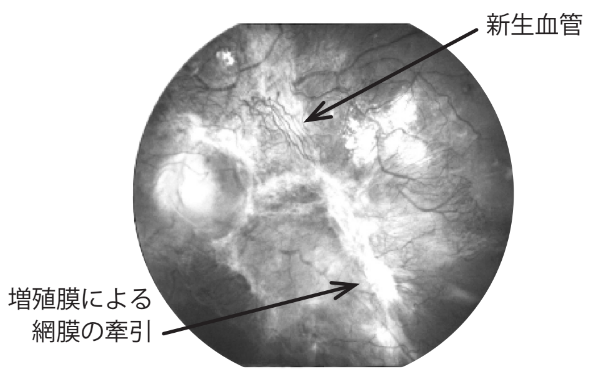

糖尿病網膜症が進行すると、網膜の血のめぐりが悪くなり、網膜に新しい血管(新生血管)が発生したり、膜状の組織(増殖膜)が網膜を引っ張って「網膜剥離 」を起こすこともあります。

進行した糖尿病網膜症の例(左眼)